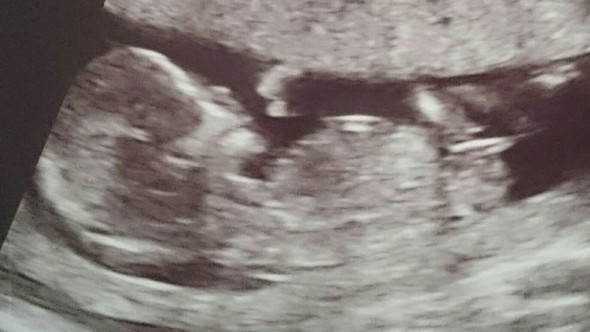

In der 15 SSW kann der Arzt im Ultraschall erkennen, ob die Schwangere ein Mädchen oder einen Jungen bekommt Beim männlichen Baby hat sich jetzt die Anlage für den Penis deutlich herausgebildet. The 15th Waffen SS, together with the 19th Waffen Grenadier Division of the SS (2nd Latvian) formed the Latvian Legion The 15th Waffen SS was swept up in the chaos of the collapse of the Eastern Front and lost much of its manpower fighting in districts surrounding Leningrad (Ostrov, Novosokolniki and Novgorod Oblast). After the unsuccessful Bundestag election in 1961 most of the former DP members left the party;.

SSW) Der Fötus ist in der 15 Schwangerschaftswoche auf eine Größe von beachtlichen acht bis elf Zentimetern gewachsen Die Ausmaße des Kindes sind damit annähernd mit einem Apfel zu vergleichen Das Gewicht des Fötus beträgt in dieser Woche um die 50 bis 70 Gramm Es nimmt gerade ziemlich schnell zu. SSW 4 mph Rain showers in the evening will evolve into a more steady rain overnight Low around 35F Winds light and variable Winds NW at 10 to 15 mph Humidity 65% UV Index 0 of 10. After the unsuccessful Bundestag election in 1961 most of the former DP members left the party;.

AllGerman Party 1961late 1960's The AllGerman Party (Gesamtdeutsche Partei / GDP) was founded in 1961 as a merger of GB/BHE and the remnants of the DP;. Größe und Entwicklung Baby In der 15SSW (140 bis 146) ist die Größe Ihres Babys durchschnittlich schon über acht Zentimeter Seine Gesichtszüge entwickeln sich in der 15 Woche allmählich zu einer charakteristischen, individuellen Form. In der 15 SSW bewegt Ihr Baby nun regelmäßig seine Arme, Beine und den Rest der Körpermuskulatur Der kleine Fetus kann sogar an seinem Daumen saugen Lesen Sie mehr über Sie und die Entwicklung Ihres Babys nach 15 Wochen.